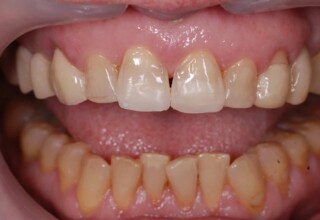

Οι όψεις ρητίνης προσφέρουν έναν οικονομικό τρόπο αισθητικής βελτίωσης της εμφάνισης των προσθίων δοντιών ενίοτε και των προγομφίων. Οι δυνατότητες τους πολλές, μπορούν να κάνουν και θαύματα! Ο μονός περιορισμός η κλινική ευχέρεια και η φαντασία του επεμβαίνοντος. Σε αυτήν την ασθενή οι τέσσερεις άνω τομείς είχαν ο καθένας το δικό του πρόβλημα(δυσχρωμία, απόκλιση) και επιπλέον: διαστήματα, πολλαπλές αποχρώσεις, κακή σχέση μεταξύ τους και με τα ούλα. Αποκαταστάθηκαν με τέσσερεις άμεσες όψεις ρητίνης (η μια πάνω σε στεφάνη πορσελάνης εμφυτεύματος!!!) οι οποίες κατασκευάστηκαν ενδοστοματικά!